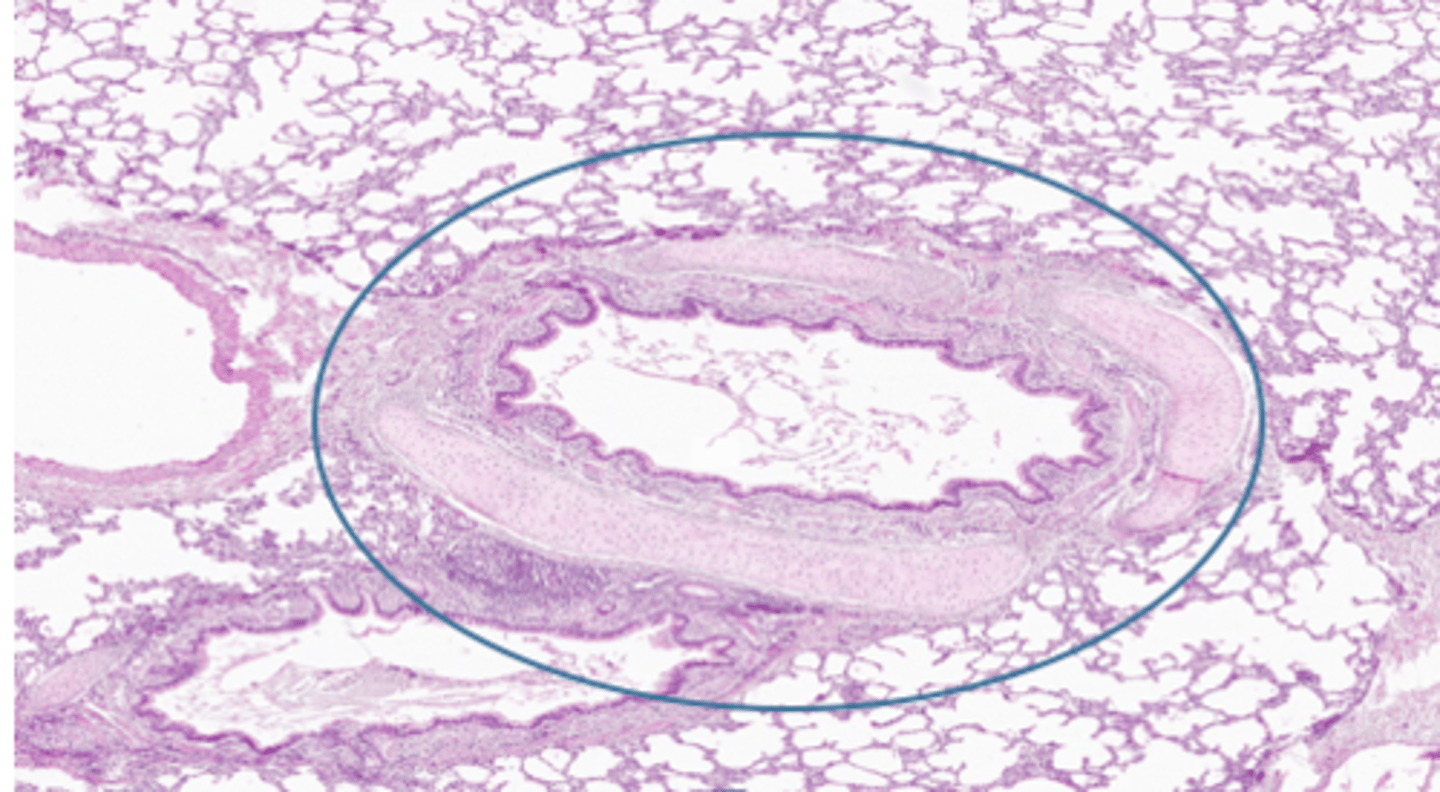

bronchioles: histology

terminal- transition from ciliated simple columnar to nonciliated simple cuboidal; goblet cells decreasing

lose goblet cells before cilia

respiratory- simple cuboidal; no cilia; no goblet cells

respiratory bronchiole histology

difficult to find- only able to distinguish if there are alveoli leading directly off them